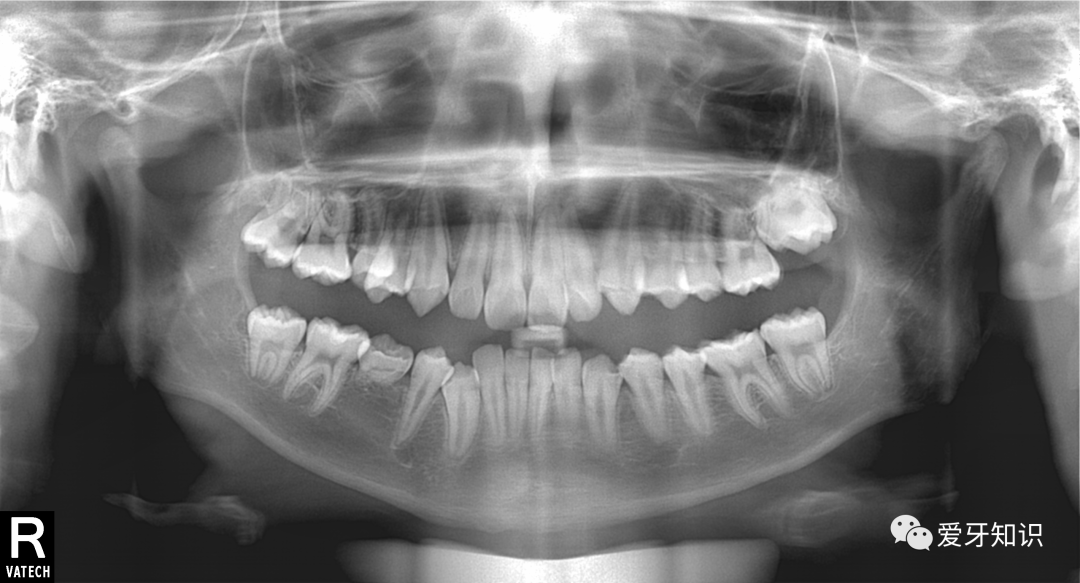

造成牙齿不整齐的原因具体能分为三种:牙性、骨性、功能性。说简单点就是牙有问题,骨头有问题,咬合有问题。网上有很多自行判断的方法,不过我还是建议拍片让医生来分析最靠谱。

拍了全景和侧位,就可以给你判断出来了。当然了,我的粉丝肯定是不收钱的了啊。免费拍全景片,侧位片,取模,设计矫正详细方案,都不要钱。只是给你多一个选择,多一份了解。